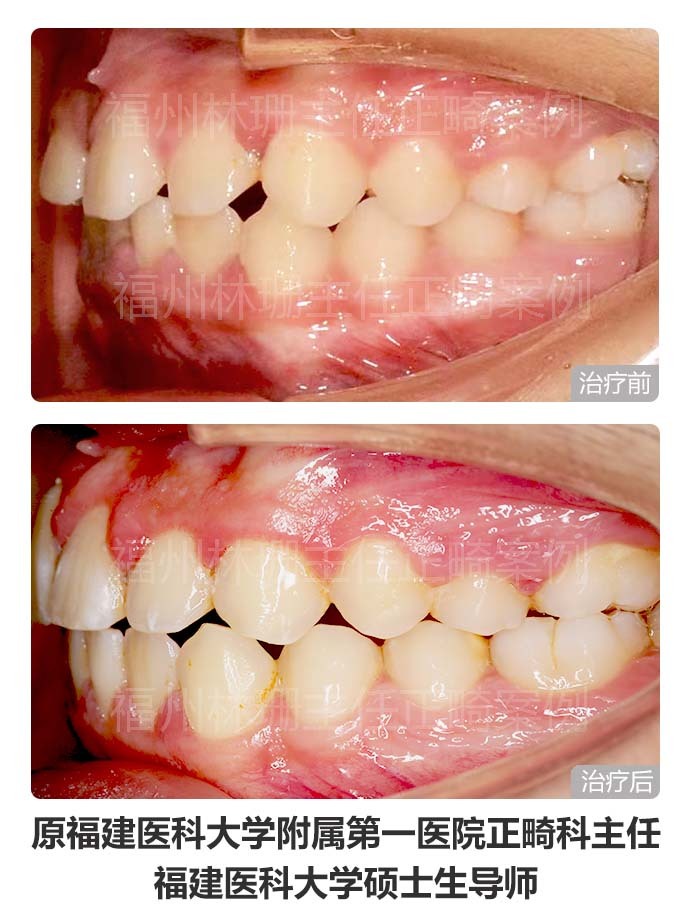

患者主诉替牙后发现上门牙未萌出,前来就诊。 检查双侧面部基本对称,侧貌直。口内检查示右上中切牙未萌出,右上侧切牙与左上中切牙存间隙。上牙列稍不齐。上中线右偏2mm,下中线正。cbct示:右上中切牙倒置阻生,合方见一多生牙。 考虑患者侧貌可,牙列拥挤度不大,且上牙列存有间隙,可通过适当扩弓拓展间隙。因此选择非拔牙矫正,利用扩弓提供的间隙牵引埋伏阻生的右上中切牙,排齐整平上下牙列,调整中线。 矫正后埋伏阻生的右上中切牙已牵引到位。上下牙列整齐,上下牙弓形态佳,上下牙弓匹配;上下前牙覆合覆盖良好,后牙咬合关系良好,上下中线正,同时维持良好侧貌。